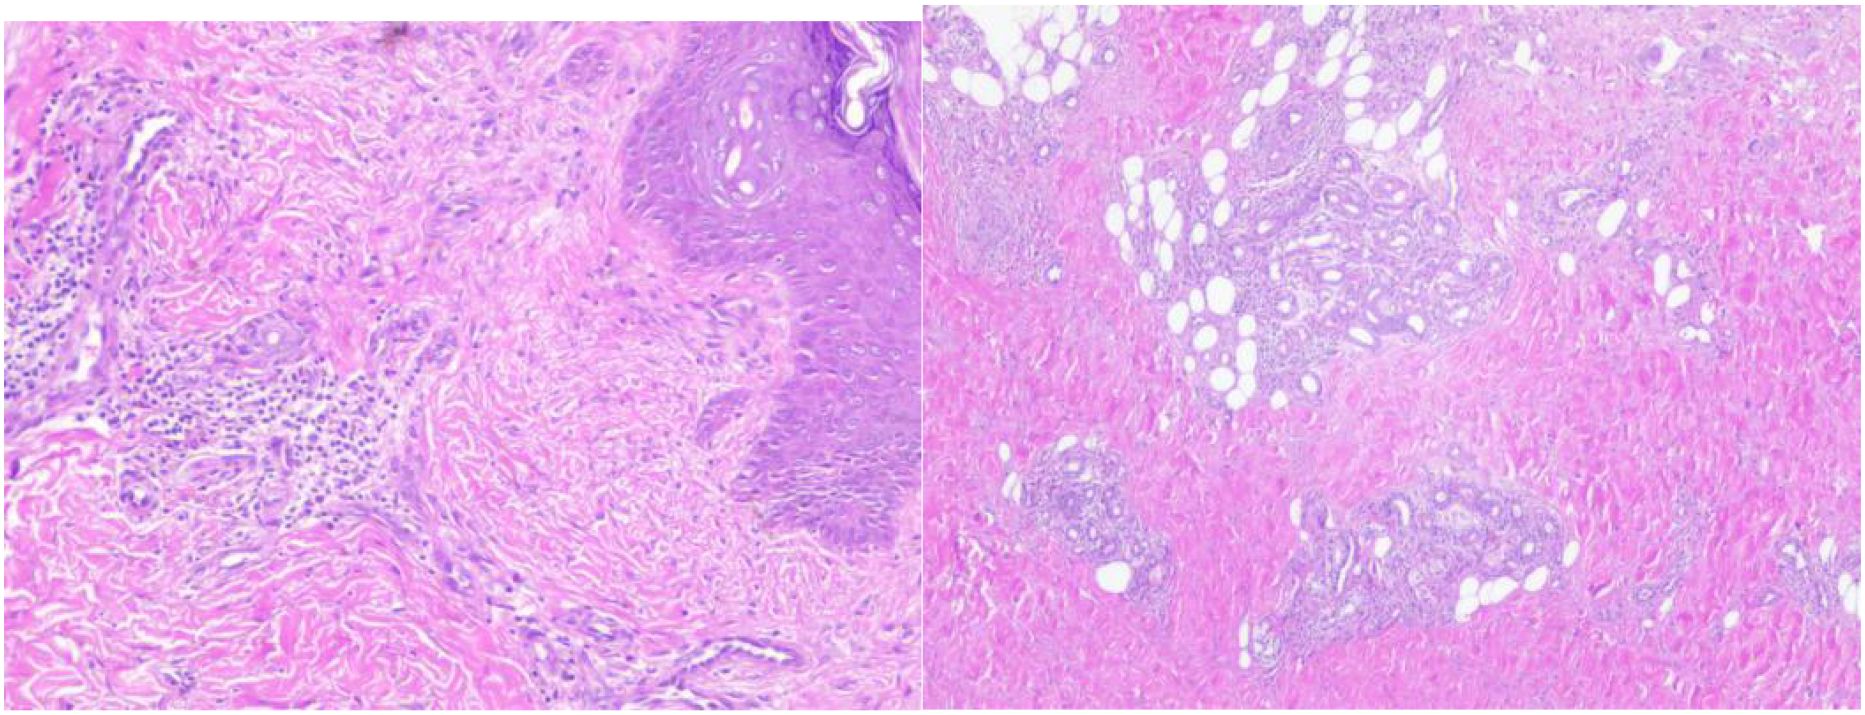

Objective This case report presents a pediatric case of eosinophilic granulomatosis with polyangiitis (EGPA) presenting with cerebella infarction as the initial symptom. The study aims to summarize the clinical features and treatment advancements of this condition, enhancing clinicians 'understanding and reducing misdiagnosis and missed diagnosis. Methods A 9-year-old male patient admitted to the Rheumatology Department of Anhui Provincial Children's Hospital was evaluated for "Dizziness, vomiting for one day, and consciousness impairment for half a day." The patient had recurrent bilateral lower limb rashes and asthma attacks over the past year. Blood tests revealed elevated eosinophil levels and IgE antibodies, while bone marrow cytology showed increased eosinophil counts. Brain MRI demonstrated cerebral infarction, herniation, and suspected thrombosis, with skin biopsy confirming vasculitis characteristics. Through retrospective analysis of clinical data and literature review, this study comprehensively summarizes EGPA's clinical features and treatment progress. Results The patient presented with cerebella infarction as the initial symptom, accompanied by central nervous system involvement, skin manifestations, hematological disorders, and vasculitis. With a history of asthma attacks, eosinophil counts during hospitalization peaked at 4.9×10^9/L (compared to baseline levels>1×10^9/L). After thorough evaluation for infections, malignancies, diffuse connective tissue diseases, immunodeficiency disorders, and inherited metabolic disorders, EGPA was confirmed. Treatment included anti-inflammatory steroids, cyclophosphamide (CTX) induction therapy, anticoagulation, followed by mycophenolate mofetil (MMF) maintenance at therapeutic doses, supplemented with rituximab. Current follow-up shows normalized eosinophil counts, restored muscle strength, resolution of skin rashes without recurrence, and favorable clinical response. Conclusion EGPA presents diverse clinical features. Cerebella infarction as the first neurological manifestation in children is rare. Eosinophilia serves as a characteristic feature. When pediatric asthma patients exhibit neurological symptoms, EGPA should be considered. For cases with central nervous system involvement, combined steroid therapy with cyclophosphamide pulse induction proves effective.